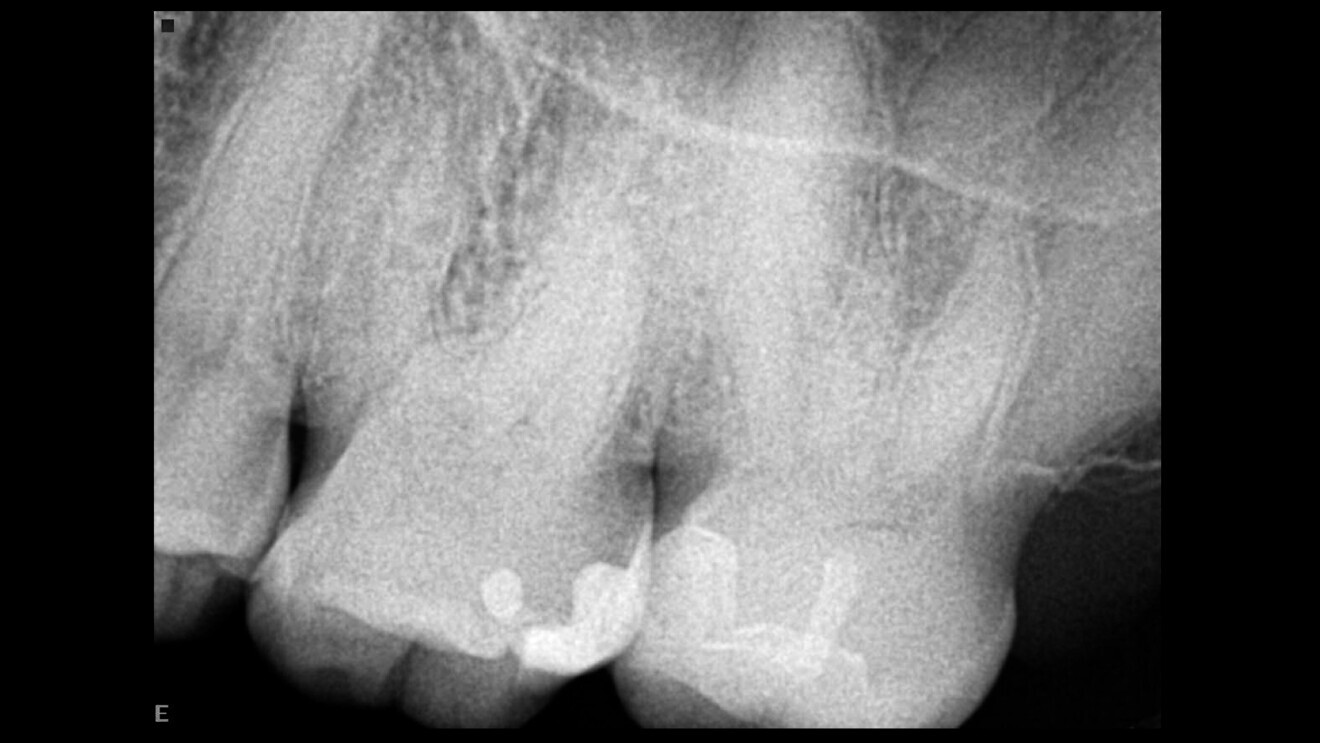

This patient attended in an emergency owing to sharp pain in a second maxillary molar. This was confirmed upon clinical examination. A standard radiograph was taken (Fig. 1), showing a very complex anatomy and calcified pulp chamber. The history of this tooth, as described by the patient, was that an inlay had been placed on it and discomfort developed after a while that had lasted several years untreated. On check-up, he had been told that everything was fine.

Fig. 1: Pre-op radiograph, showing a very complex root canal system and a calcified pulp chamber.